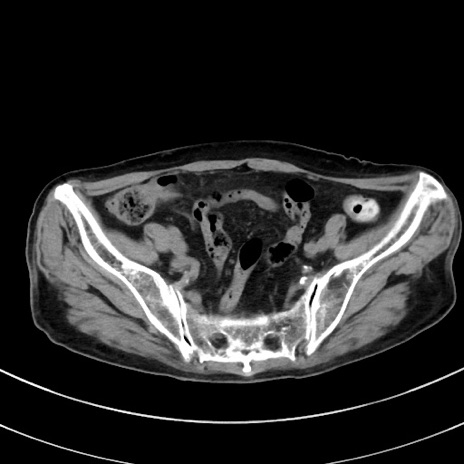

冠状断像

【症例】70歳代 女性

【主訴】心窩部痛

【現病歴】延髄病変の精査・加療にて神経内科入院中。本日より心窩部痛あり。

【既往歴】虫垂炎

【身体所見】右下腹部を中心に圧痛と反跳痛あり。

【データ】WBC 10900、CRP 0.02